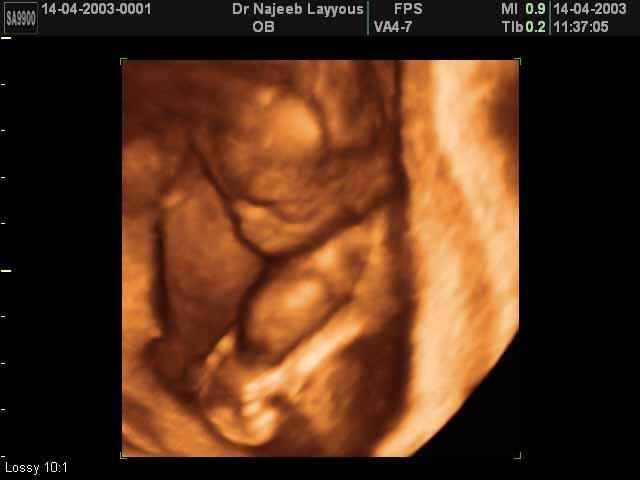

3D second trimestre échographie Photos de numérisation - deuxième partie de la grossesse